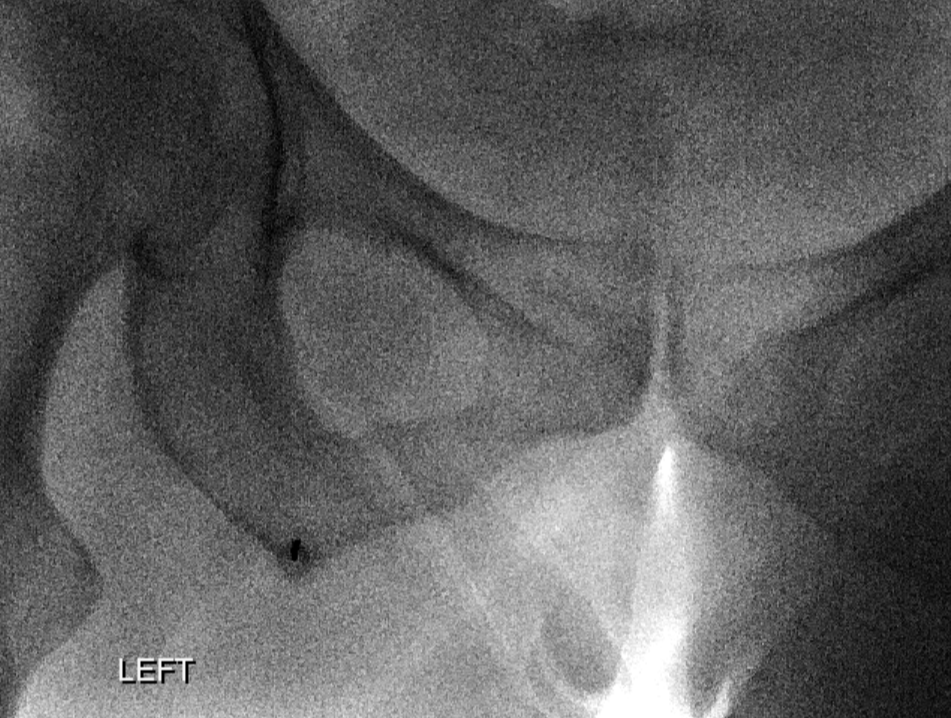

3. Common Hamstring Tendon Injection